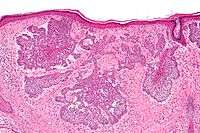

Basal-cell carcinoma, nodular type

- Nodular basal cell carcinoma includes most of the remaining categories of basal-cell cancer. It is not unusual to encounter heterogeneous morphologic features within the same tumor.

- Nodular basal cell carcinoma (also known as "classic basal-cell carcinoma") most commonly occurs on the sun-exposed areas of the head and neck.[5]:748[6]:646